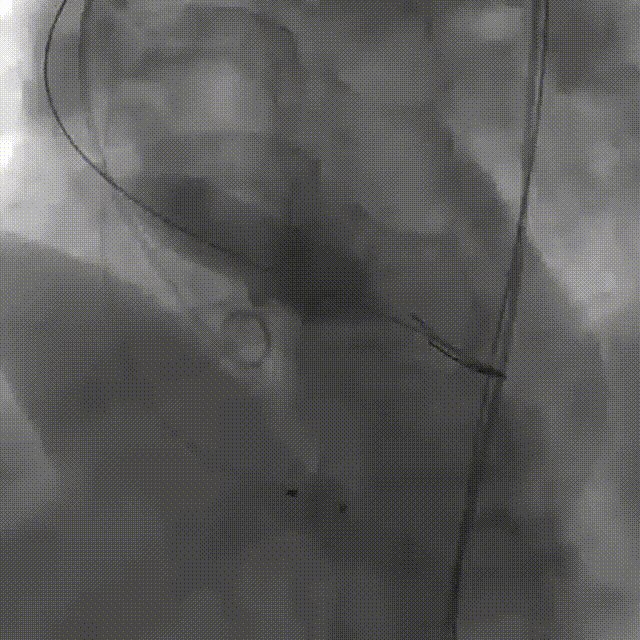

彭小平教授 南昌大学第一附属医院 不断探索医疗可能,筑牢患者长期保障 TAVR 治疗的终极目标,不仅是完成一次手术,更是为患者构建长期稳定的生命保障,而瓣膜耐久性是直接关乎患者后期是否需要二次手术的关键所在。全球首款预装干瓣的问世,为临床提供了全新的选择方案。厂家的15 年质保承诺,是源于材料研发的突破与临床验证的底气。从临床角度,如未来瓣膜可以耐久15年,则可大大减少患者反复就医的身心负担与经济压力,本质上是为患者的长期健康 “投保”。 人生的每一次选择,都需要慎重。相信在行业的前行中,我们不断探索医疗的可能性,让每一次治疗都能真正护航患者长远健康! 患者病史 主诉与现病史:3 年前开始出现胸闷、气促,活动后(如上楼、上坡)症状加重,休息后可缓解,当地医院心脏彩超提示主动脉瓣狭窄,未予特殊治疗;2 年前发现血压轻度升高,口服阿奇沙坦片(40mg,每日 1 次)降压,血压控制尚可;近 1 个月胸闷气促症状明显加重,2025 年 10 月 13 日外院心脏彩超提示主动脉瓣重度狭窄,为进一步诊治入院。 既往史:高血压病史 2 年,规律服用阿奇沙坦片(40mg qd);1 年余前因外伤致腰椎骨折,保守治疗后痊愈;有慢性阻塞性肺疾病病史;有胃窦糜烂、十二指肠球部溃疡史,2023 年曾发生急性上消化道出血;有真菌性食管炎、多发性结肠息肉病史。 术前超声提示:主动脉瓣钙化,主动脉瓣狭窄(重度),左室肥厚,升主动脉增宽。 二尖瓣反流(轻度),三尖瓣反流(轻度),肺动脉瓣高压(轻度)。 左室舒张功能减低,收缩功能正常,左室射血分数 74.7%。 术前CT:Type0型二叶瓣,瓣叶增厚并极重度钙化,钙化主要分布在瓣叶基底部,延伸到左室流出道。主动脉瓣环径24.8mm;升主动脉狭窄后扩张至主动脉弓,双侧瓣叶开口高度可,窦部空间可,STJ内径增宽,升主动脉内径可,预估冠脉低风险;主动脉水平夹角49.1°,非横位心;主动脉弓角、弓距可;“自杀左室”,建议术前补液,ECMO湿备,术中注意循环崩溃。 外周双侧入路内径可,髂总动脉有零星散状钙化,双侧股动脉均能通过20F大鞘,右股低分叉。 手术策略:推荐使用右侧股动脉为主入路,左侧股动脉为辅助入路;右股分叉上方1cm穿刺;推荐使用18mm球囊预扩,预装AV23瓣膜。 手术过程:在右股动脉穿刺建立通路后,顺利送入大鞘,经食道超声及血管造影确认路径稳定。18mm球囊预扩后评估冠脉灌注良好,后将Prostyle A® AV23瓣膜精准释放于目标位置,20mm球囊后扩,超声显示轻微瓣周漏,术后即刻造影显示无明显反流,峰值压差由术前的80mmHg降至12mmHg,心功能明显改善,患者生命体征平稳。 18球囊预扩无腰无漏 输送器跨瓣顺利 定位 平稳释放瓣膜 20球囊后扩 最终造影,位置良好,轻微瓣周漏 Prostyle A®预装干瓣——助力临床最优化解决方案 1、流入端桶状设计:流入端桶状的设计,锚定迅速,有效减少释放步骤,提升植入稳定性; 2、平衡的收腰设计:二叶瓣小心室患者对瓣膜径向支撑力提出更高要求,Prostyle A®均衡的收腰设计可更好适应小瓣环及不规则瓣口结构,保证了EOA,有效降低了循环崩溃风险,提高瓣膜的耐久性; 3、预装干瓣 便捷顺安:金仕生物专利抗钙化技术运用纳米技术去除组织内的细胞碎片和磷脂,封闭游离醛基,从根本上阻断了瓣膜钙化的多项因素,显著提升了瓣膜的耐久性;同时,相比较传统戊二醛保存方式,干式存储最大限度的保留心包的亲水亲油平衡,还原组织天然曲柔性,进一步保障了瓣叶开合,保证长期耐久性; 专家简介 彭小平 南昌大学第一附属医院(点击查看专家详细简历) · END ·